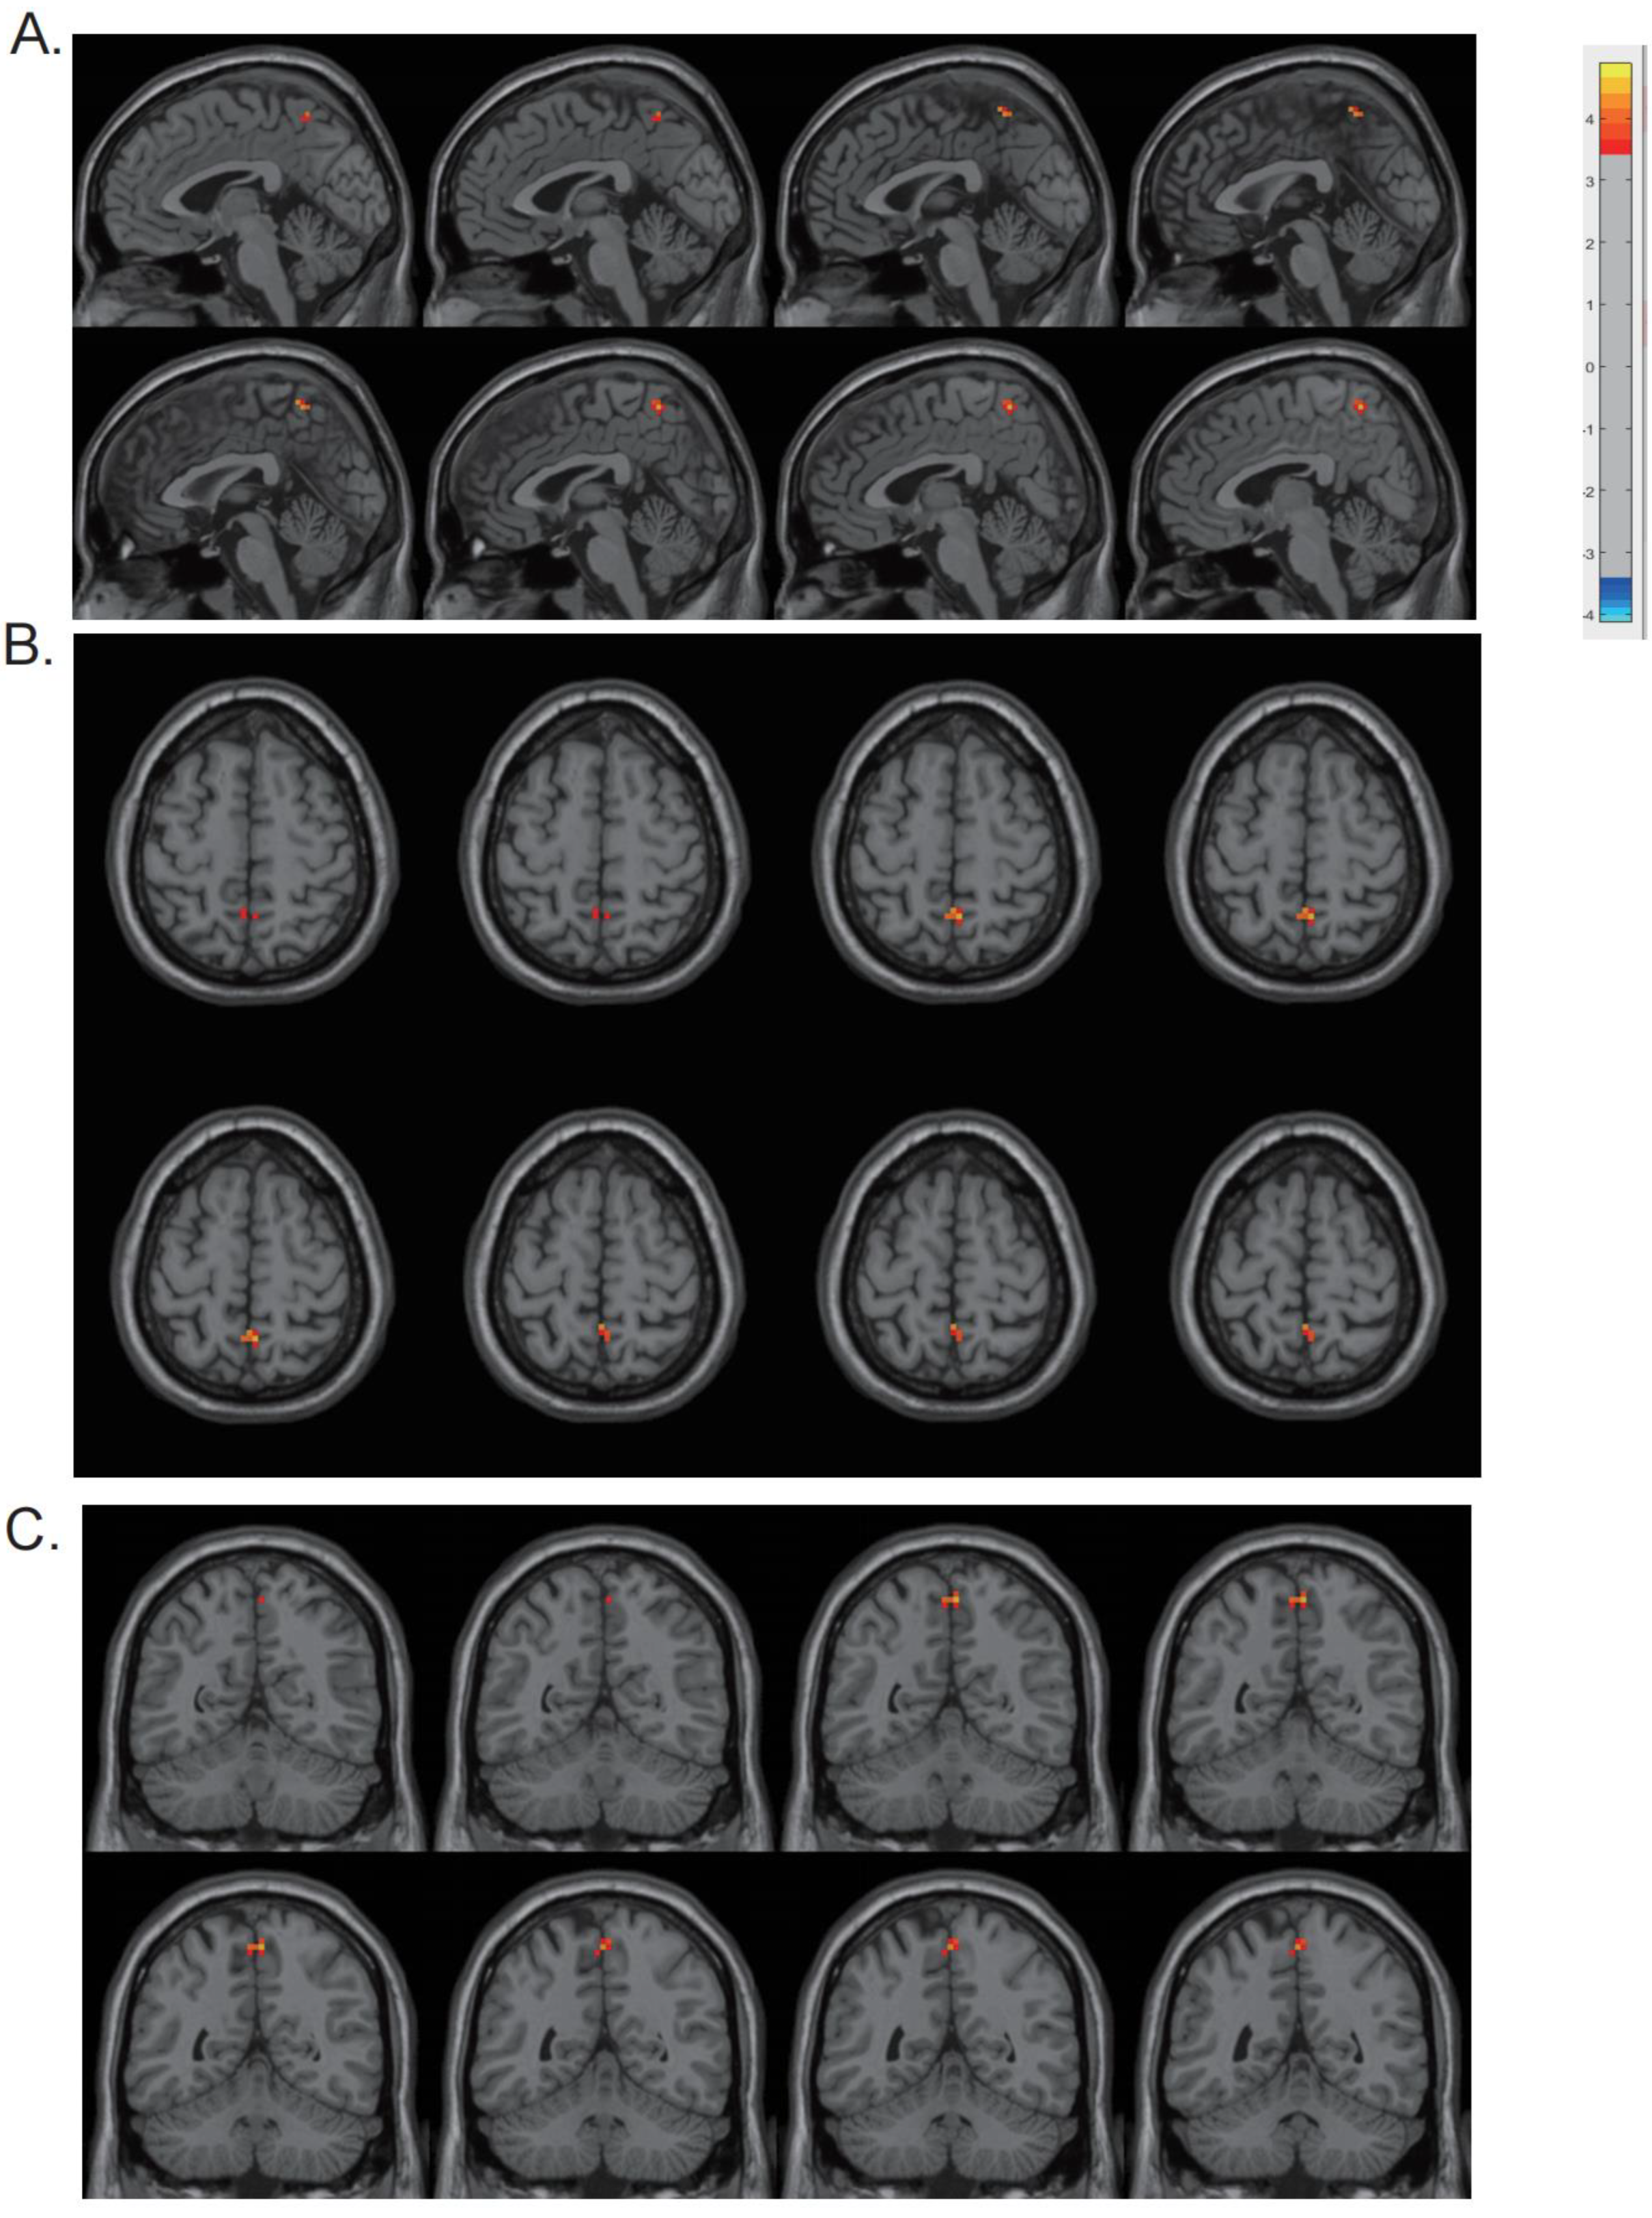

The CV of dReHo was substantially higher in the precuneus in PD patients than in HCs (p < 0.001) (Table 3 and Figure 2). The cluster size was 13 voxels. The CV of dReHo in the precuneus was significantly correlated with HAMD, HAMA, and NMSQ scores (r = −0.441, −0.312, and −0.345; p = 0.001, 0.018, and 0.009) in PD patients (Figure 3). There were no significant correlations between altered dReHo and disease duration, disease severity (H-Y staging and UPDRS score), or MMSE score. To verify whether the correlations between altered dReHo and HAMA, HAMD, and NMSQ scores were due to a common association between disease progression, we performed partial correlation analyses while controlling for disease duration as a covariate, and the results remained consistent with those obtained without controlling for disease duration. In addition, for better control of the contribution of other parameters, we performed multiple linear regression analysis, with altered dReHo as the dependent variable and age, education, head motion (mean framewise displacement (FD), introduced by Jenkinson et al. [28]), and UPDRS, MMSE, HAMA, HAMD, and NMS scores as independent variables. In the multiple linear regression analysis, we found that the HAMD score was the only parameter with statistical significance. The standardized coefficients beta value was −0.403, the significance (sig.) was 0.04, and the 95% confidence interval ranged from −0.008 to 0. This result suggested that there was a significant association between altered dReHo and HAMD score after controlling for other factors, such as UPDRS, head motion parameters, age, and education level.

Figure 2.

Differences between groups in terms of dReHo variability. The CV of dReHo in the precuneus was found to be higher in the PD patients, as shown in sagittal (A), transverse (B), and coronal (C) views.